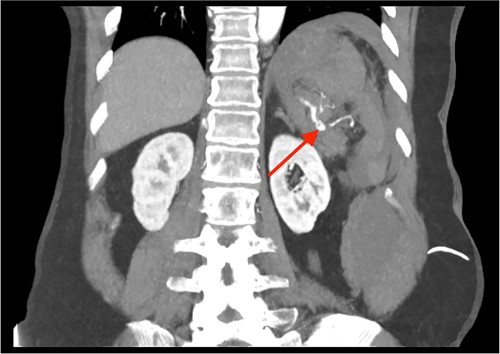

Triple-phase computed tomography (CT) of the abdomen and pelvis revealed a sizeable acute haematoma in the left upper abdomen, below the gastric fundus and body, alongside the pancreatic tail and splenic hilum, extending amongst the proximal small bowel mesentery and into the left subphrenic space. The origin of the haemorrhage appeared to arise from the left upper quadrant. There was a pseudoaneurysm in close proximity to the pancreatic tail and splenic hilum, apparently arising from the adjacent distal splenic artery. CT scan did show local contrast extravasation into the haematoma, as mentioned above (Figs 1–3).

CT angiography of the abdomen with 3D reconstruction. Ruptured SAP.